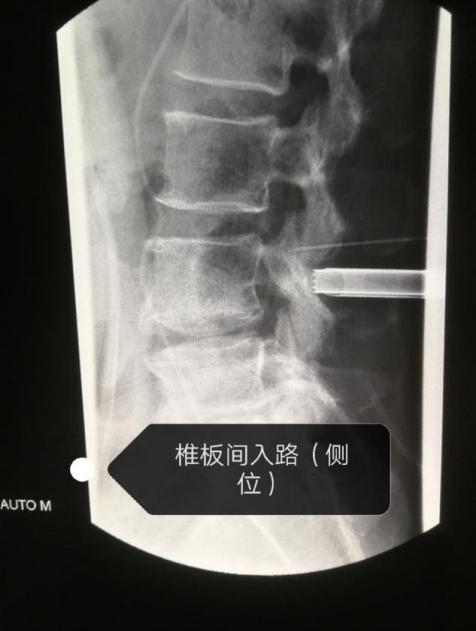

在介入放射科手术室,杨主任团队应用疼痛科关键技术——脊柱内镜技术,在局部麻醉下通过椎板开窗入路,脊柱内内镜下腰椎间盘髓核摘除术、椎间孔狭窄镜下椎间孔成型术、镜下脊神经后支松解术,成功摘除脱出游离腰椎间盘髓核。手术效果立竿见影,朱女士疼痛症状明显缓解,术后即可下床行走,5天后痊愈出院。

手术过程图示

杨四海介绍,该病例较特殊,在诊断及治疗上都有一定难度,遇到影像诊断与症状体征不相符合时,要进一步查找原因。腰椎间盘突出症、髓核沿椎管向上游离脱出较少见,微创手术难度较大。我们可以通过病灶靶点上下脊神经走行区,采用局部麻醉,内镜下可视环锯及椎板咬骨钳行椎板开窗入路,变换通道位置,摘除脱出游离髓核,解除患者腰腿痛、腰椎间盘突出症、盘源性腰痛等。